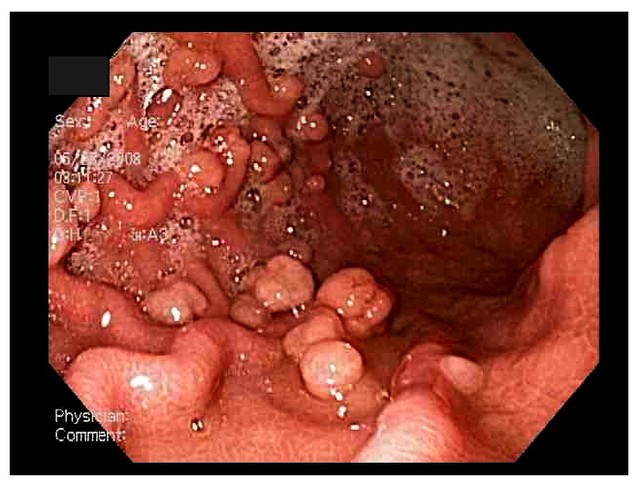

Nguy cơ trở thành ung thư của khối u tăng sản là rất nhỏ, nhưng những khối u có đường kính lớn khoảng 2cm trở lên thì có nguy cơ trở thành ung thư.Hình ảnh polyp dạ dày thông qua nội soi dạ dày.

- Fundic polyp tuyến: Được hình thành từ các tế bào tuyến bên trong lớp lót bên trong dạ dày. Loại khối u này không có khả năng trở thành ung thư dạ dày ngoại trừ trường hợp xuất hiện ở người có sẵn hội chứng ung thư ruột kết.